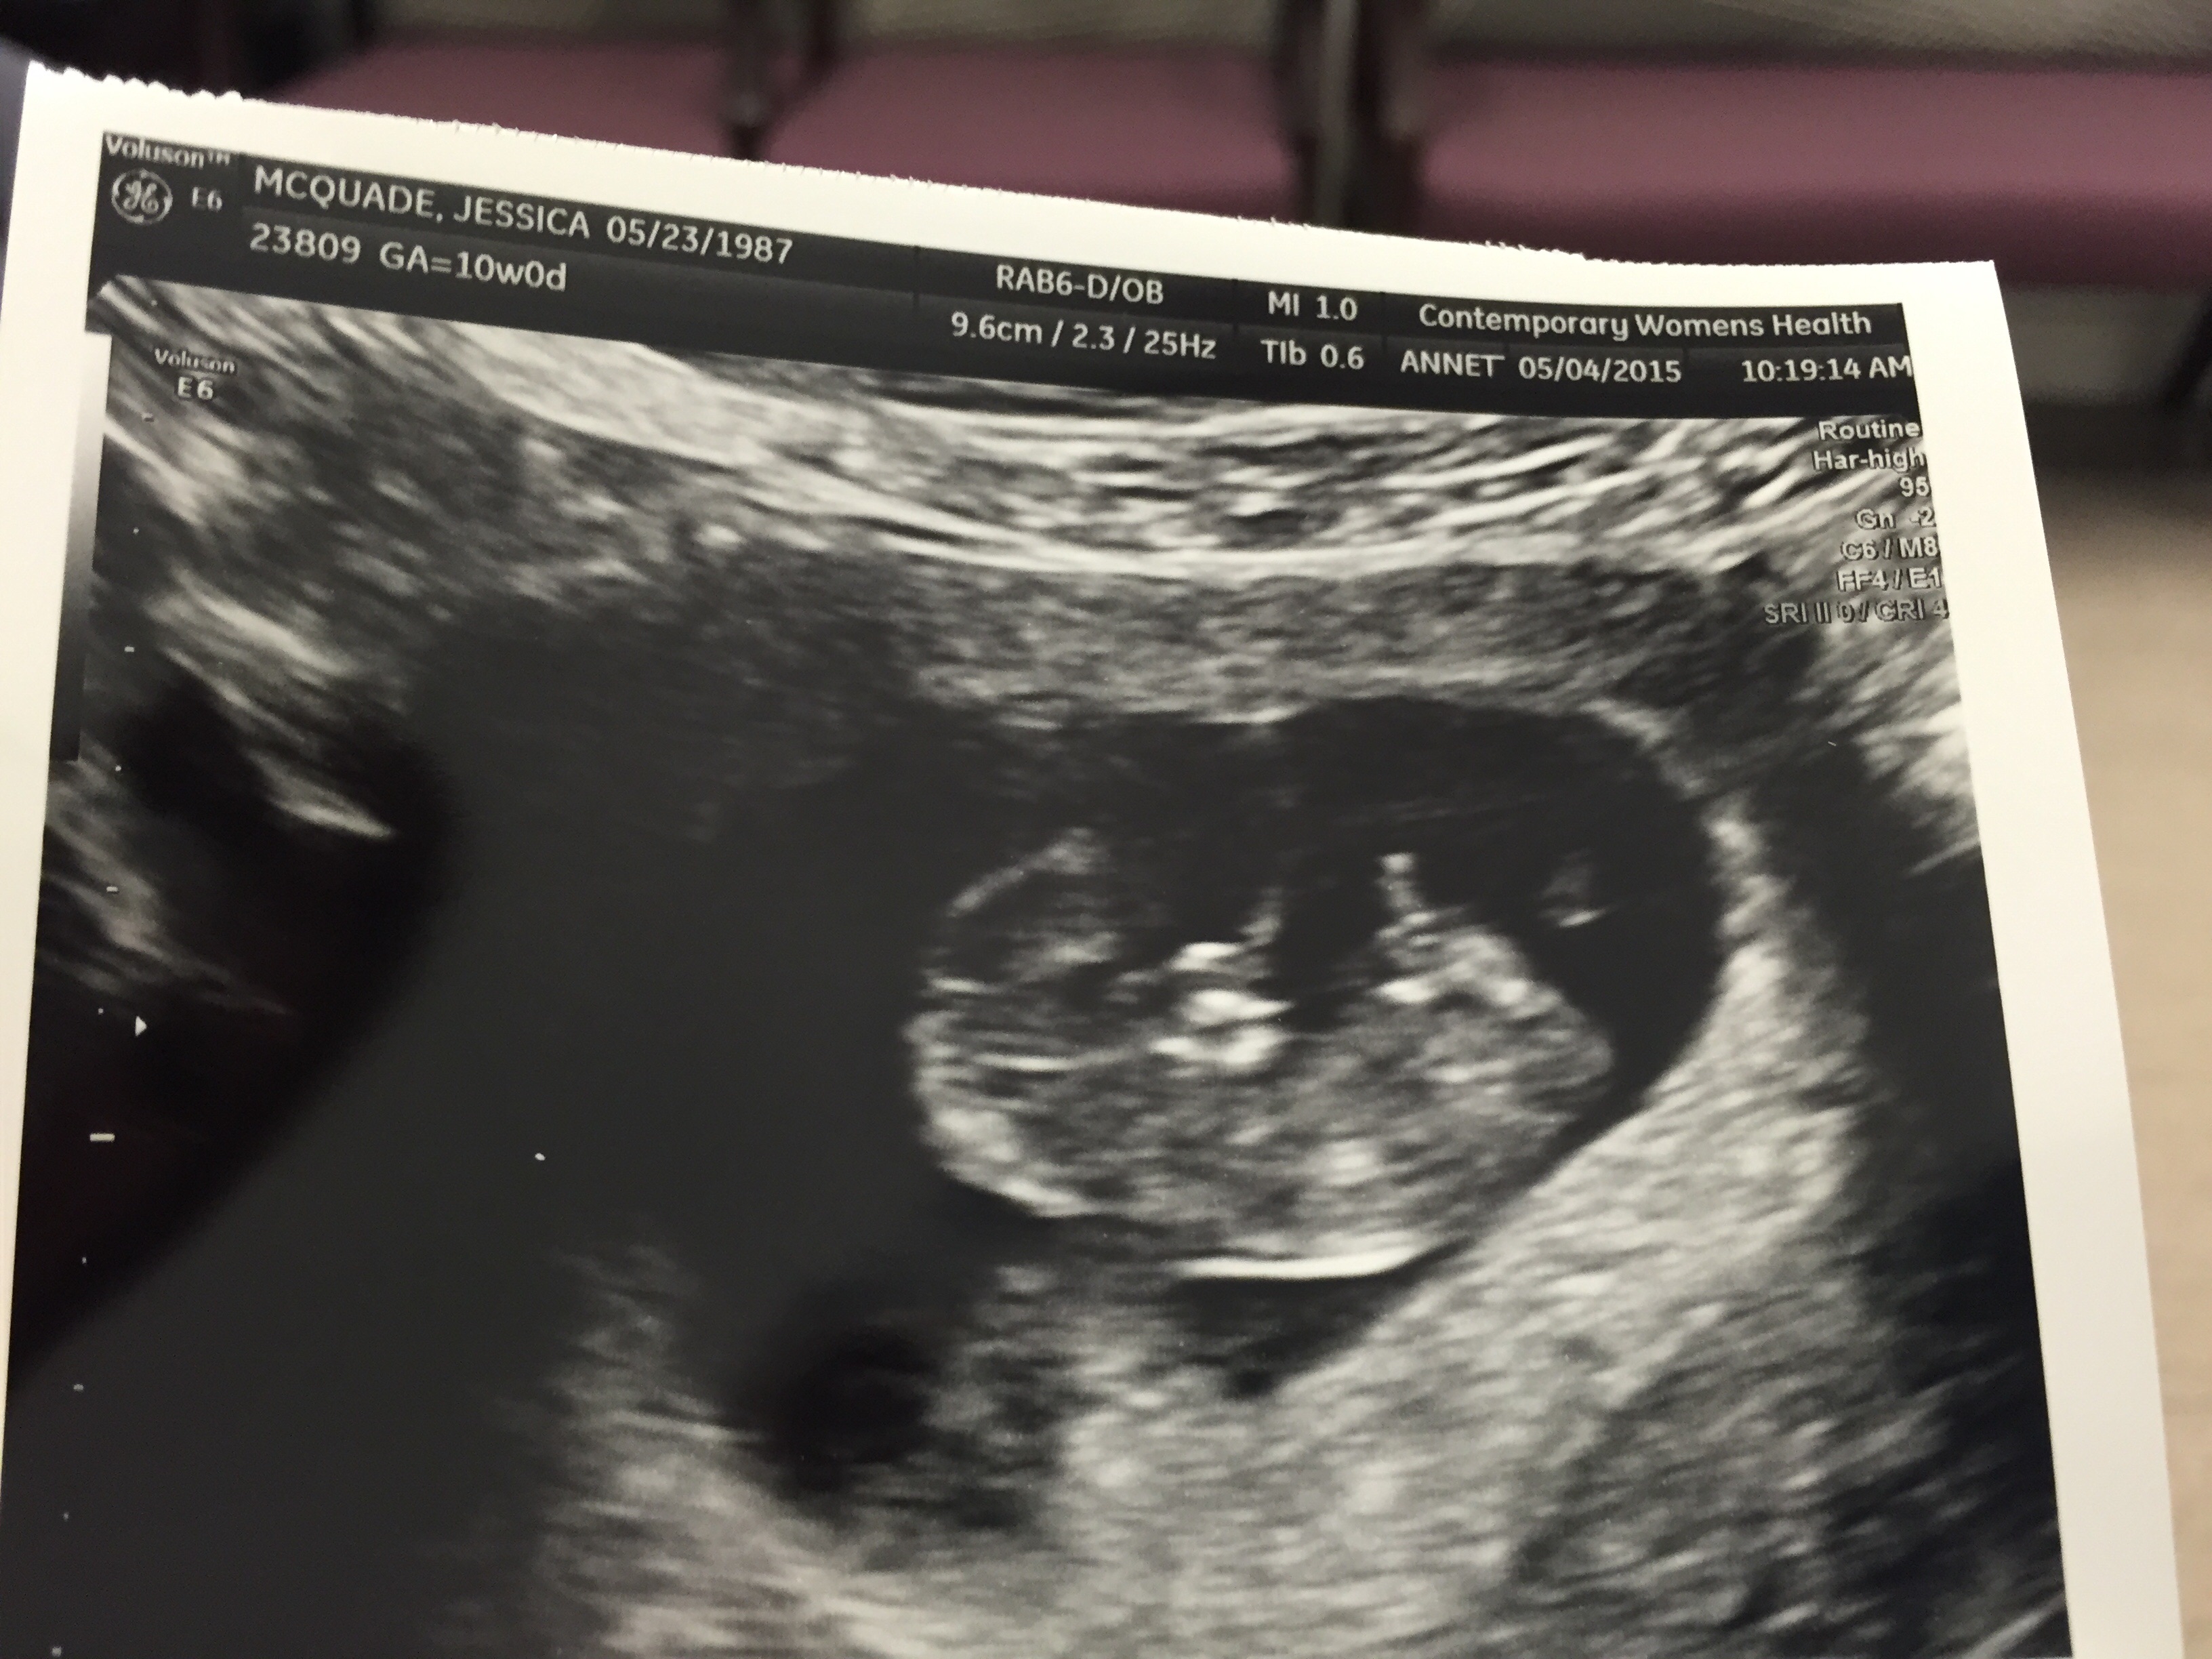

10 weeks 4 days yesterday.... Was waving and squirming all over... HR was 173.... So amazing... Get genetics test results and gender back in 7-10 business days!